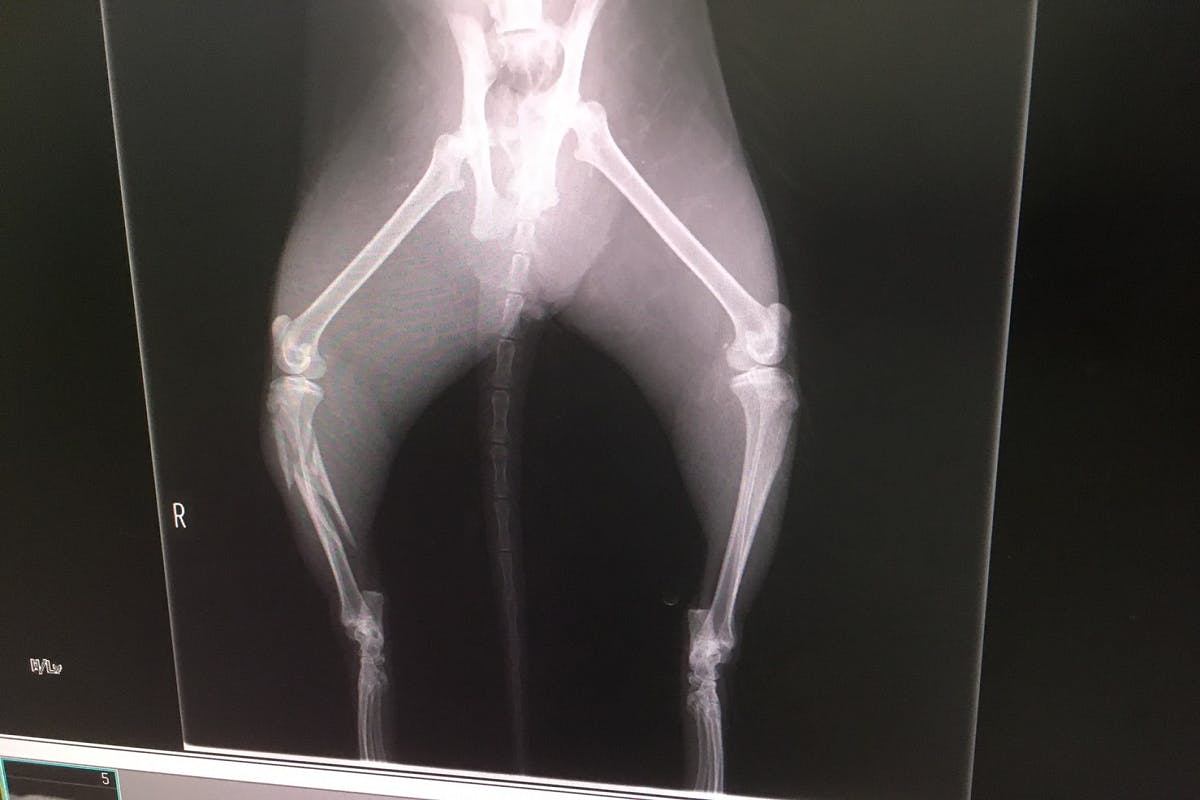

レントゲンでの診断の結果

骨盤骨折(腸を圧迫して排便できないかもしれない)

脛骨複雑骨折

重度の貧血

膿が溜まっている。

獣医師の診断は虐待ではなく事故だろう。膿の様子から事故してから1週間

くらいは経過しているだろう